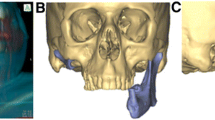

Case 4: Mandibular Tumor Surgery

This 16-year old female was referred for evaluation and surgical management of a rapidly expanding pathologic lesion of the mandible (juvenile ossifying fibroma), which had failed multiple previous procedures by other surgeons. This lesion also had significant facial and lingual expansion. Due to the destruction of the native mandible and the loss of normal anatomic contour, the decision was made to obtain a SLA model of the mandible to assist in planning a staged reconstruction (Fig. 4a). Once the model was received, the gross alteration in normal architecture was appreciated. A laboratory bur was used to reduce the model back to “normal” form based on corrected cephalometric tracings. This model was then used as the foundation for pre-bending a reconstruction plate to near normal contour (Fig. 4b). The patient was then taken to the operating room where a resection and mandibular reconstruction procedure was performed. This patient’s postoperative course was complicated by an infection of the bone graft; however, she has subsequently undergone successful final reconstruction with re-grafting (Fig. 4c).

a SLA model demonstrating significant bony expansion of the mandible by a rapidly growing and extensive pathological lesion. b A reconstruction plate has been pre-bent and adapted on an osteoconductive framework which will later house the autogenous bone grafts. c Post-operative panoramic radiograph results of bone grafting with optimal bone volume